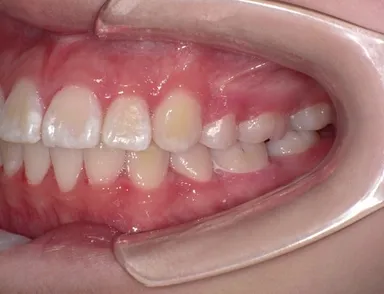

患者は13歳8か月の女子。主訴は左上に八重歯があること。上顎両側、下顎左側第一小臼歯を同時抜歯し、JET systemで治療を行ったところ動的治療期間は7か月であった。前歯部のトルクコントロール、上下顎正中の一致、咬合関係の改善が行われた。抜歯により誘発されたRAPを利用したJET systemでの治療は、治療期間の短縮に寄与し、患者QOLを向上させることが示唆された。

7か月後

この症例のように身体の成長途上にある中高生であれば、治療を6~9か月で終えることができる可能性があります。歯列矯正治療では、平均して治療に2~3年にわたることが一般的ですが、JET systemによる最も顕著な患者さんのメリットは治療期間の短縮です。長期にわたる治療のストレスや生活の制約、ブラケットによる見た目への懸念、矯正装置の使用にともなう不快感を短期間で終えることができます。また、JET system専用に開発したブラケットを使用することで、これまでよりも弱い矯正力で治療を行うため痛みが少なくなります。JET systemは、患者さんのモチベーションを維持し、治療効果や患者さんの満足度向上につなげることが期待できます。